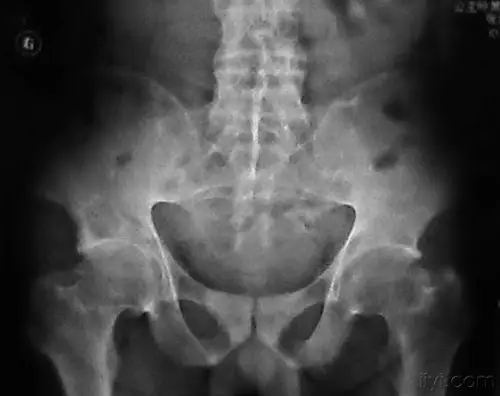

强直性脊柱炎的影像学表现及训练方法

强直性脊柱炎典型骶髂关节改变